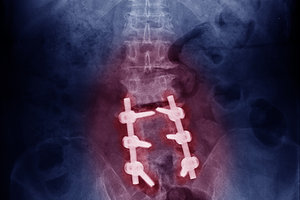

Plain-film imaging is the most cost-effective assessment of lumbar degenerative changes. They are inexpensive, easy to obtain, give good assessment of the AP spinal canal diameter, and current high-speed systems have low levels of radiation. MRI is the diagnostic test of choice when additional information is needed concerning pathology, disc integrity, canal shape and adjacent soft tissues.

Clinical Tip: Radiographs of the lumbar spine need to be weight-bearing to assess the impact of axial load on the degenerative spine. For example, the extent of slippage in a degenerative spondylolisthesis may not appear in a recumbent film. Use an MRI center that performs upright or seated studies, and with both, consider flexion/extension studies.